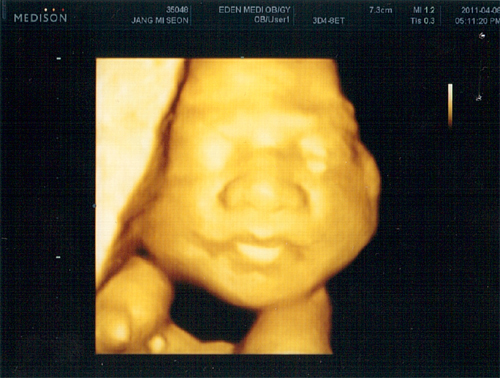

26주 4월 8일(금) 입체 초음파사진

글쓴이 : 최고관리자 날짜 : 11-04-09 09:39 조회 : 487